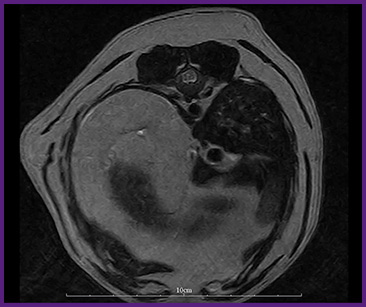

我們提供留院服務並擁有相應的治療設施,亦是小數備有CT電腦掃描及MRI磁力共振等大型醫療儀器的診所及醫院。